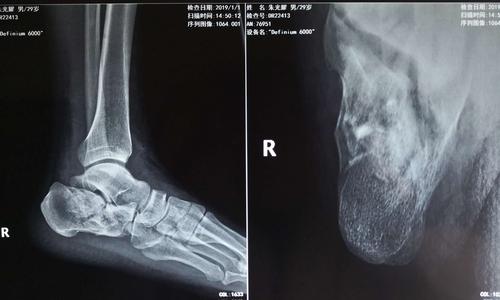

【喜讯】我院成功开展首例跟骨骨折跗骨窦切口微创手术

请问这例跟骨骨折的治疗方案

跟骨骨折关节镜下微创治疗

10岁小孩跟骨x光片